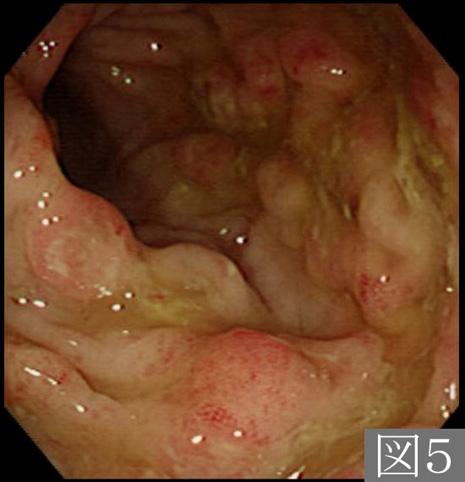

症例提示(所在地,施設名等): 福岡県・ 九州医療センター (平賀聖久先生、原田直彦先生、村中光先生からの提供症例)

疾患(病理主体)の分類炎症性・潰瘍性疾患/アメーバ赤痢

部位(臓器別)大腸/2区域以上の大腸にまたがるもの

検査方法内視鏡

病変の最大径(ミリ)10〜14